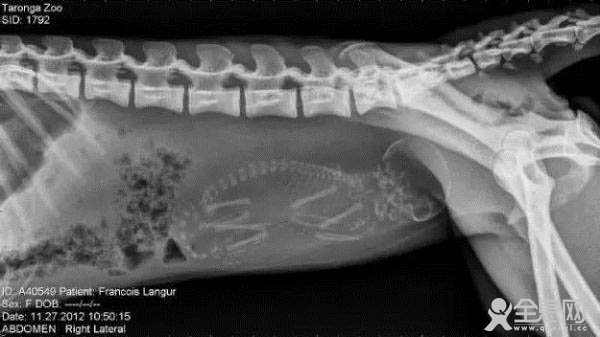

怀孕的猴子。肚子里的小猴宝宝,不仔细看后面的尾巴。还以为是人类呢。